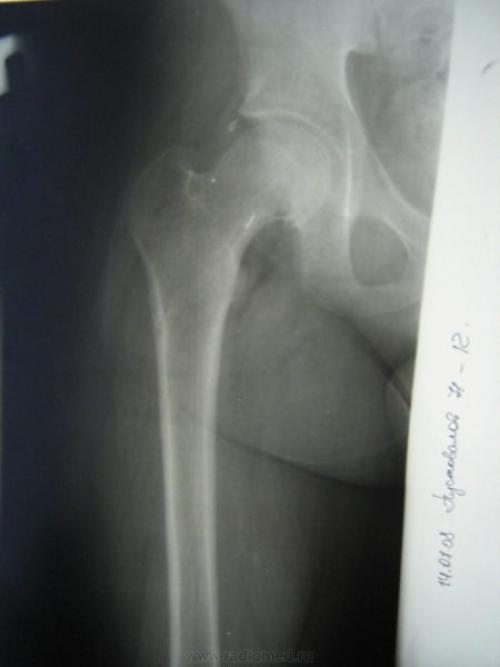

- Перелом шейки бедренной кости. Такой диагноз часто ставится женщинам, достигнувшим 60 лет. Причиной такого повреждения тазобедренного сустава является банальное падение или целенаправленный удар в область тазобедренного сустава. В момент перелома чувствуется очень резкая боль, усиливающаяся при движении. Неприятные ощущения начинают отдавать во внутреннюю поверхность бедра. В месте повреждения появляется отек, синяк над областью тазобедренного сустава. Поврежденная левая или правая нога становится короче, а у человека развивается хромота, сустав начинает щелкать. Кроме того, травма способствует защемлению нерва, поэтому бедро начинает неметь.